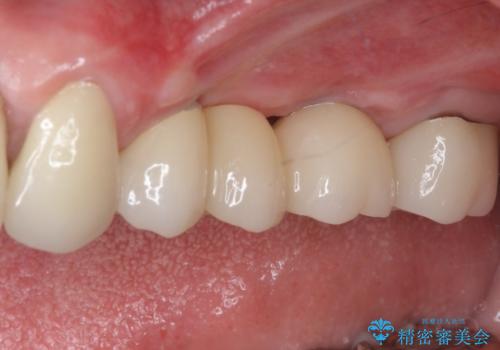

手術後は処置部に痣や腫脹が出現したり、痛みが出たりしましたが、補綴治療後は咬み合わせが安定し、大変満足していただきました。